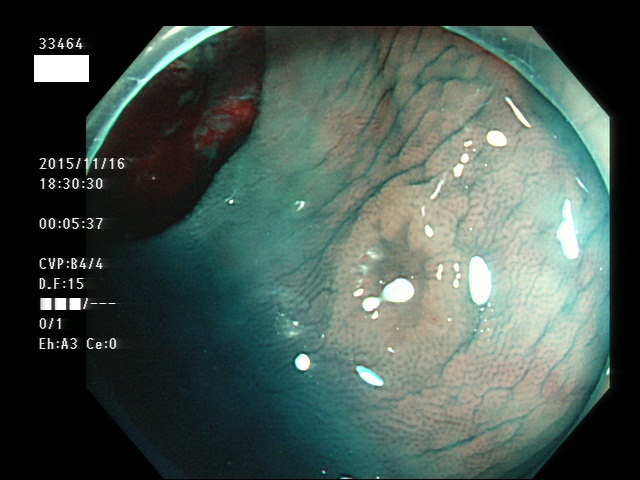

上記100名より抽出した平坦・陥凹型腺腫(=癌化の危険が高いが見落としやすい病変)の内視鏡写真